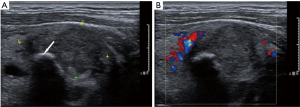

The dominant sonographic findings of PTL were large (average 4.8±1.7 cm, range 1.6–8.7 cm), solid (100%), ill-defined (81.5%) mass with echogenic strands (92.6%), posterior echo enhancement (85.2%) and without calcification (100%) (Table 2), while the dominant sonographic findings of ATC were large (average 5.8±2.1 cm, range 2.5–11.0 cm), solid (100%), ill-defined (100%) mass with macrocalcification or microcalcification (80%) (Table 2). PTL cases presented with diffuse type (25.9%) (Figure 1), nodular type (48.2%) (Figure 2) and mixed type (25.9%) (Figure 3). All ATC cases presented with nodular type (100%) (Figures 4,5). There is no significant difference in thyroid size, nodular size, margin, shape, echo texture, cystic change and vascularity on sonography between ATC and PTL groups (Table 2).

With regard to tumor-spreading patterns, in 15 patients with ATC, 13 patients had extra-thyroid extension into the surrounding soft tissue (Figure 4A), 1 patients invaded trachea, and 2 patients invaded jugular vein. In 27 patients with PTL, 14 patients had extra-thyroid extension into the surrounding soft tissue (Figures 2A,B,3B), 1 patients invaded trachea (Figure 1C).

Another typical sonographic feature for PTL is linear echogenic strands. In our study, most of PTLs presented with echogenic strands (25/27, 92.6%), and only one lesion (1/15, 6.7%) of ATC presented with echogenic strands. Some studies suggested that sonographic findings of PTL were correlated with pathologic findings. Orita et al. (33) and Nam et al. (29) indicated that the hypoechoic areas of PTL were consistent with lymphoepithelial lesions containing neoplastic cells, whereas echogenic structures within or around the lesions were consistent with fibrotic tissue and normal thyroid tissue. Ota (9) reported a destructive linear pattern which might suggest the transformation of MALT lymphoma into a high-grade malignant lymphoma. In their study, all of the 15 MALT lymphoma of the head and neck presented with echogenic structures whereas two DLBCLs of thyroid showed linear echogenic strands and one DLBCL of parotid gland showed destructive linear echogenic strands, and the remaining 13 DLBCLs showed no echogenic strands. However, in our study, all (8/8) MALTs and 73.3% (11/15) of DLBCLs had linear echogenic strands, and 2 DLBCLs had destructive linear strands.